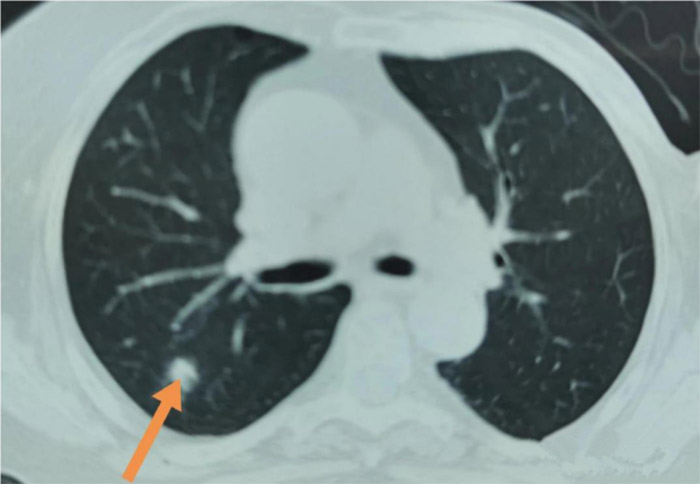

这位阿姨75岁,体检发现右肺上叶结节,直径约1.2cm,边缘欠规则,无毛刺及分叶,无胸膜牵引。体检中心的医生说,最好到正规医院看一下。

阿姨带着胸部CT片子和满心的焦虑来到了丹东市第一医院胸外科门诊,我院的医生在仔细查看胸部CT后,认为单从CT影像上看,这属于一个不确定性结节,建议阿姨化验“肺小结节自身抗体检测”,看看有没有激发肿瘤免疫反应。

“肺小结节自身抗体检测”结果回报各项指标均为阴性,考虑恶性趋势不明显。结合影像学和检验学看,这个结节可以随访观察。

过了3个月阿姨来复查,胸部CT没有看见任何病灶,她的肺结节完全不见了。阿姨高高兴兴的离开了胸外科诊室。